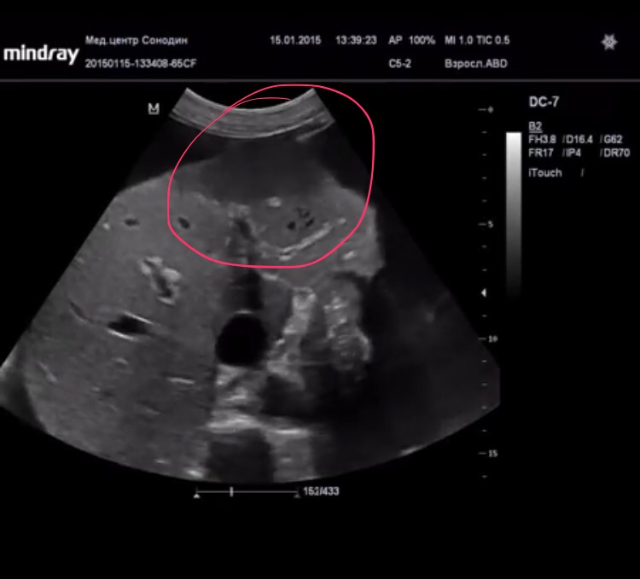

потому что выявлена только жидкость в брюшной полости, а ее причина нет

я не увидел того чего хотел бы увидеть в контексте асцита(нпв, перикард, плевральные), поэтому для меня эта кинопетля не информативна